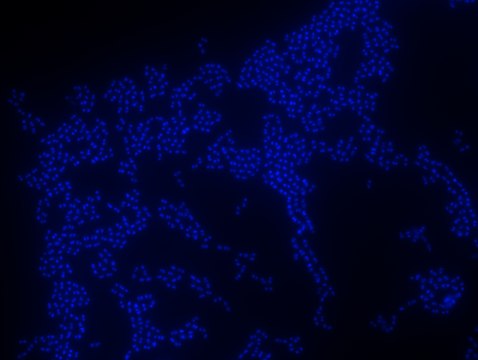

Enterococcus faecium FISH probe – ATTO 488

Probe for fluorescence in situ hybridization (FISH), 20µM in water

Fluorescent In Situ Hybridization technique (FISH) is based on the hybridization of fluorescent labeled oligonucleotide probe to a specific complementary DNA or RNA sequence in whole and intact cells. Microbial FISH allows the visualization, identification and isolation of bacteria due to recognition of ribosomal RNA also in unculturable samples. FISH technique can serve as a powerful tool in the microbiome research field by allowing the observation of native microbial populations in diverse microbiome environments, such as samples from human origin (blood and tissue), microbial ecology (solid biofilms, aquatic systems) and plants. It is strongly recommended to include positive and negative controls in FISH assays to ensure specific binding of the probe of interest and appropriate protocol conditions. We offer positive (MBD0032/33) and negative control (MBD0034/35) probes, that accompany the specific probe of interest. Enterococcus faecium probe specifically recognizes E. faecium cells,. E. faecium a gram-positive bacterium and is a cause of a variety of infections, including endocarditis, urinary tract infections, prostatitis, intra-abdominal infection, cellulitis, and wound infection as well as concurrent bacteremia. Studies have shown that E. faecium is highly resistant to multiple antibiotics and that vancomycin-resistant Enterococcus faecium (VRE) can be asymptomatically carried by healthy people, which can hamper hospitals’ attempts to control the spread of the bacteria. Over the past two decades, Enterococcus faecium has emerged as a leading cause of multidrug-resistant enterococcal infection in the United States. E. faecium has a high antibiotic-resistance with more than half of its pathogenic isolates expressing resistance to vancomycin, ampicillin, and high-levels of aminoglycosides.

Probe for fluorescence in situ hybridization (FISH), recognizes Enterococcus faecium cells